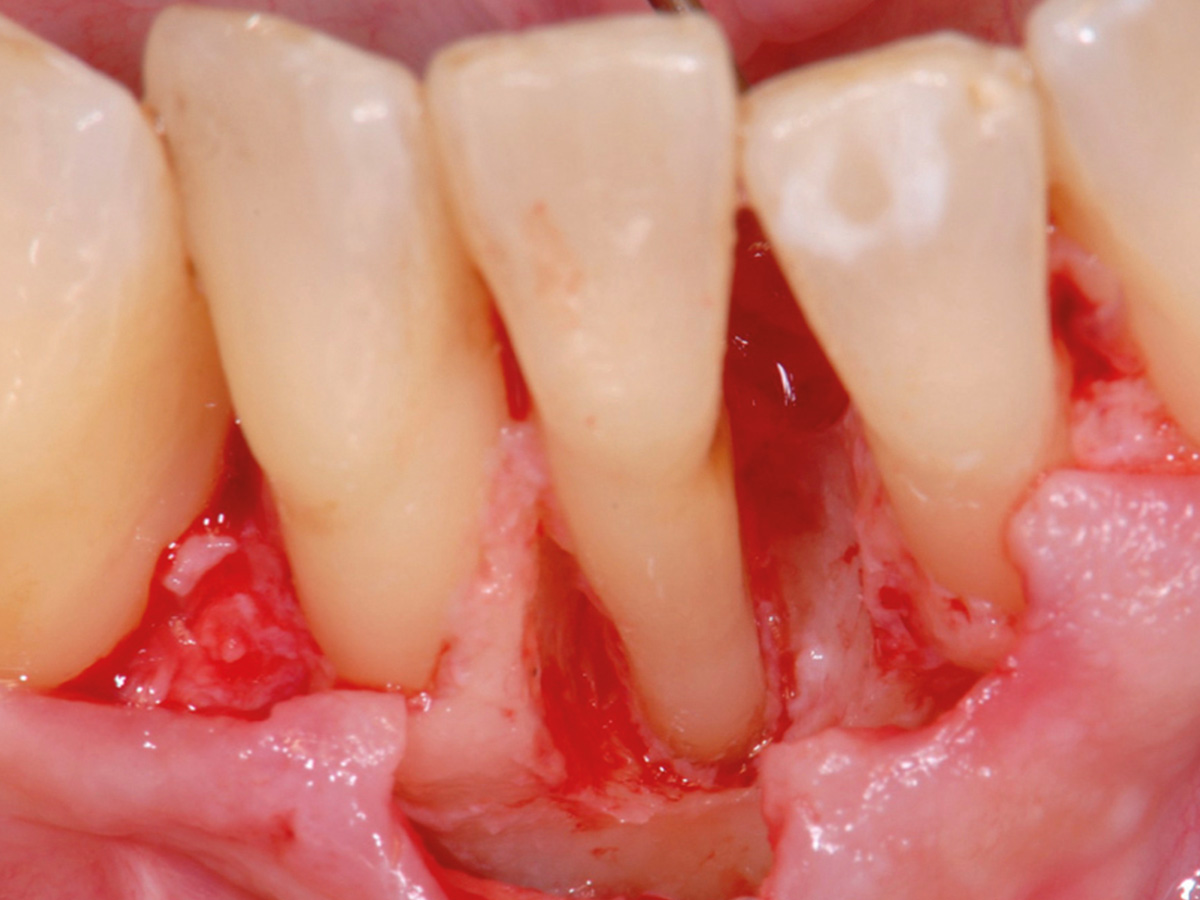

Nach der nicht-chirurgischen Parodontitis-Therapie verbleiben an stark parodontal-kompromittierten Zähnen häufig noch Resttaschen, die im Rahmen einer erfolgreichen Parodontitis-Therapie weiter behandelt werden müssen. Zu diesem Zeitpunkt stellt sich also die Frage, ob der einzelne Zahn mittels parodontalchirurgischer Verfahren erhaltungsfähig ist oder doch besser extrahiert werden sollte. Regenerative parodontalchirurgische Verfahren spielen an dieser Stelle eine große Rolle. Doch wann sollte welche chirurgische Technik, wann sollten welche regenerativen Materialien verwendet werden? Der Workshop vermittelt Kenntnisse, wann ein Zahnerhalt mittels Regeneration parodontaler Defekte erfolgreich möglich ist und wann welche chirurgischen Techniken und regenerativen Materialen zielführend sind.

HANDS-ON

Die Teilnehmer trainieren am Tiermodell verschiedene mikrochirurgische Techniken der Parodontalchirurgie. Zusätzlich werden die Schritte regenerativer Maßnahmen an unterschiedlichen Defekten (z.B. an 1-, 2- und 3-wandigen Defekten) mit den verschiedenen regenerativen Materialien geübt.